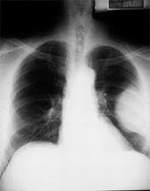

It's is a rare form of cancer that attack the layers of mesothelial cells, which form the thin lining (mesothelium) of the lung, chest, abdomen, and heart organs. The role of the mesothelium is to protect these organs by producing a lubricating fluid. The mesothelium found in the chest cavity is called the pleura and the mesothelium in the abdominal cavity is referred to as the peritoneum. The mesothelium that surrounds the heart is known as the pericardium. Almost all cases of this disease are linked to exposure to asbestos.

Is the most common form . Pleural mesothelioma begins in the chest cavity and affects the lungs. The most common way for pleural mesothelioma to present itself is through pleural effusion. The initial symptoms that a patient will experience due to the pleural effusion are dyspnea (difficulty breathing), chest pain and/or persistent cough some patients show no symptoms at all. Less common symptoms include fever, night sweats and weight loss.